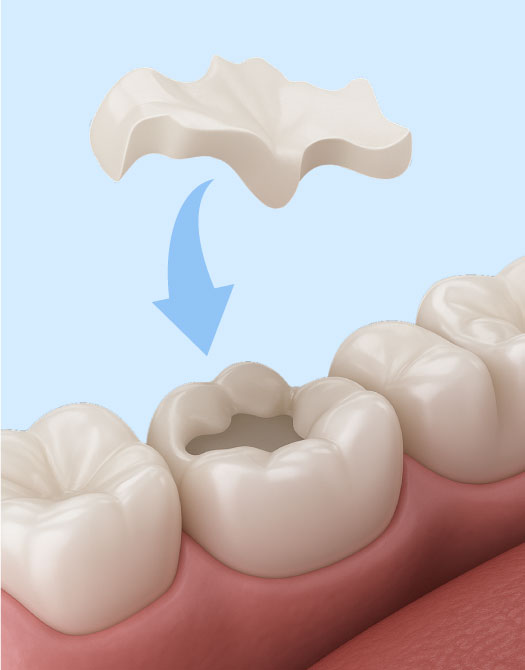

К микропротезам относят адгезивные мостовидные конструкции и протезы «бабочка», виниры ортопедические и терапевтические, керамические и металлические вкладки и пр. Микропротезы изготавливают в зуботехнической лаборатории, поэтому они идеально «садятся» на зубы, а их форма и оттенок соответствуют натуральным зубам.

Протезирование керамическими вкладками показано в тех случаях, когда установка пломбы не представляется возможной. Для заполнения кариозной полости, увеличения высоты коронки или восстановления функционала зуба вкладка является идеальным вариантом.